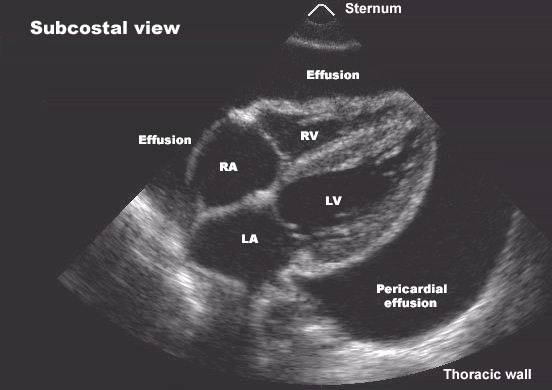

Pericardial effusion can be caused by pericarditis, malignancy, tuberculosis, uremia, hypothyroidism, trauma, autoimmune diseases, or post-cardiac surgery.

Pericardial effusion progresses to cardiac tamponade when intrapericardial pressure rises enough to impair cardiac filling, leading to hypotension, elevated jugular venous pressure, and reduced cardiac output.

Key signs include hypotension, elevated jugular venous pressure, tachycardia, muffled heart sounds, and pulsus paradoxus. Echocardiography confirms the diagnosis.